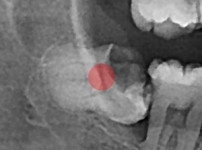

严重龋坏的智齿